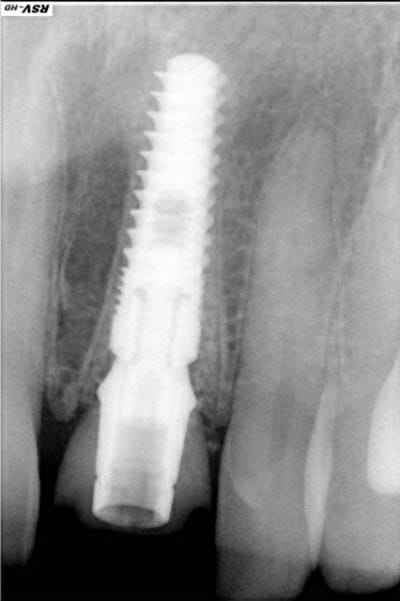

Voilà ce que l'on arrive à faire mais ce fut limite!

Interactive dx8dv8 - Eugenol